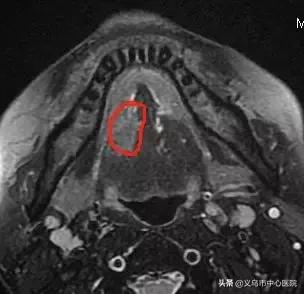

“大概5个月前,舌头被槟榔划了个口子,我也没在意。”可过去了好几个月,王先生舌头上划破的口子非但没有愈合,周围也变得硬邦邦的,疼痛感较强。看到“割脸人”新闻,他突然慌了,担心自己患上口腔癌的他来到了中心医院口腔科,组织活检最终确诊为“舌鳞状细胞癌”。

▲ 入院时,磁共振显示王先生的肿瘤范围